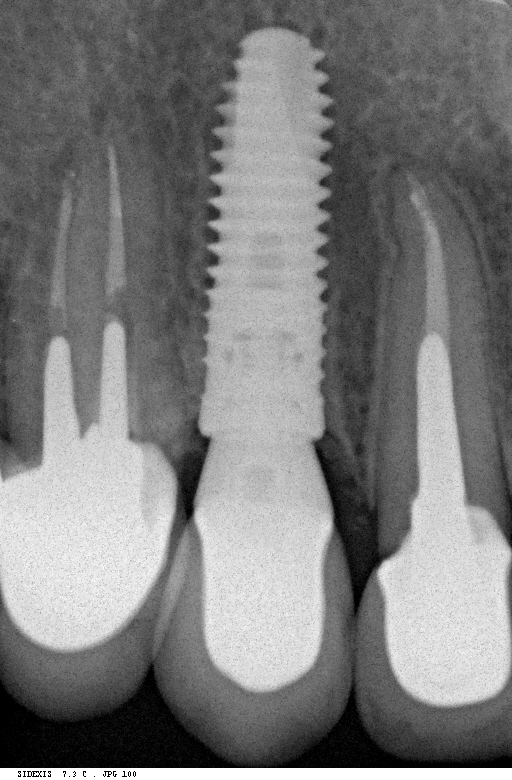

Исследование на рентгене после имплантации зубов

Раздел: Снимки-откровения